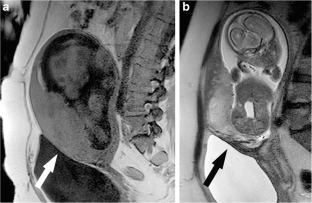

Fig. 1

Fig. 2

Fig. 3

Fig. 4

Fig. 5

Fig. 6

Fig. 7

Fig. 8

Fig. 9

Fig. 10

Fig. 11

Fig. 12